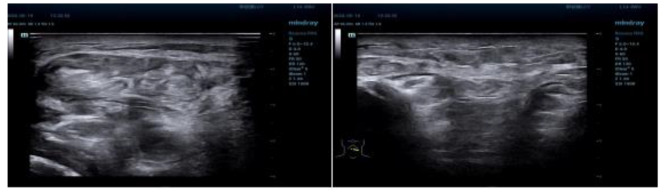

Case presentation: We report a 51-year-old male, diagnosed with lung adenocarcinoma 2 years ago, presenting as swelling and hardening of the face and neck. The patient was diagnosed with carcinoma en cuirasse from lung cancer and was transferred to the oncology department for further management. Unfortunately, the patient gave up treatment after 3 months and died after 1 year of follow-up.